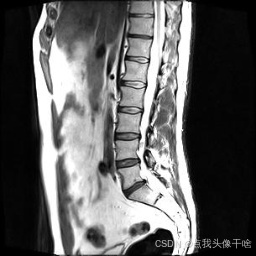

想象一下,你给AI看一张脊椎的核磁共振(MRI)照片,它就能像经验丰富的医生一样,把照片里每一块骨头、每一节椎间盘都给你清清楚楚地标记出来。这个系统干的就是这个酷炫的事儿!

- 原图:就是一张张脊椎的MRI扫描图。